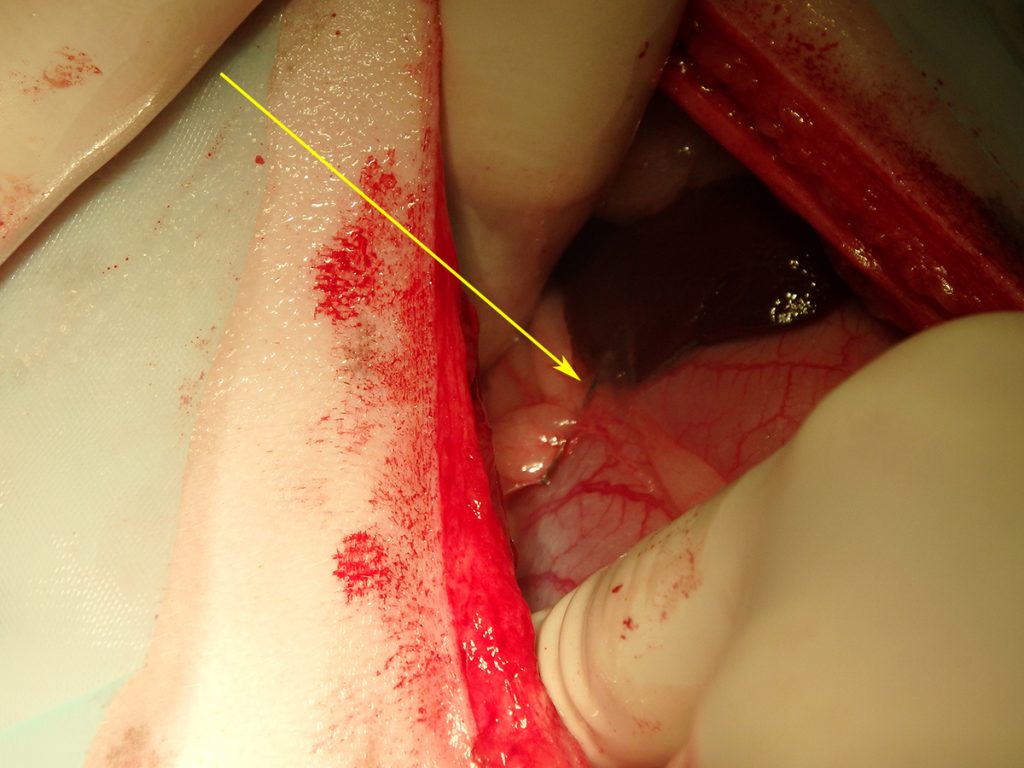

Na het openen van de buik en het verwijderen van wat vet, is de chirurg gaan zoeken. Al snel vindt hij aan de voorzijde van de maag een vreemd vliesje. Dit blijkt een stukje vet en vlies te zijn, wat op het oogje van de naald verkleefd zat. Ruim 2/3 van de naald blijkt in een leverlob te zitten. De naald blijkt er niet eenvoudig uitgetrokken te kunnen worden. Hij zit aardig vast. Dit suggereert dat hij er misschien al iets langer zit. Bij het verwijderen van de naald ontstaat er een klein scheurtje in de lever. De bloeding kan worden gestelpt met een speciaal matje dat stolling bevordert. Hierna is het een kwestie van de buik sluiten en Lady mag weer wakker worden.